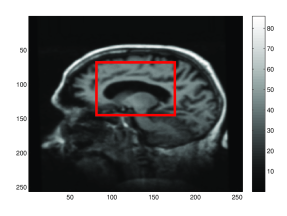

In this paper, we use higher-order momentum distributions in the LDDMM registration framework to obtain a deformation parametrization that increases the capacity of sparse approaches with a basis consisting of interpretable elements. We show how the higher-order representation model locally affine transformations, and we use the compact deformation description to register points and images using very few parameters. We illustrate how the deformation coded by the higher-order momenta can be directly interpreted and that it represents information directly useful in applications: with low numbers of control points, we can detect the expanding ventricles of the patient shown in Figure 1.

The expanding ventricles can be registered by placing deformation atoms in the center of the ventricles of the fixed image as shown in Figure 1. For each patient, we manually place five deformation atoms in the ventricle area of the first baseline 3D volume. It is important to note that though we localize the description of the deformation to the deformation atoms, the atoms control the deformation field throughout the ventricle area. Based on the size of the ventricles, we use 3D Gaussian kernels with a scale of 15 voxels, and we let the regularization weight in (1) be . The effect of these choices is discussed below. Each deformation atom consists of a zeroth and first-order momenta. We use similarity to drive the registration [9]555See also http://image.diku.dk/darkner/LOI. and, for each patient, we perform two registrations: we register the two baseline scans acquired at the same day, and we register one baseline scan against the follow up scan. Thus, the baseline-baseline registration should indicate no ventricle expansion, and we expect the baseline-follow up registration to indicate ventricle expansion. Figure 1 shows for one patient the placement of the control points in the baseline image, the follow up image, the -Jacobian determinant in the ventricle area of the generated deformation, and the initial vector field driving the registration.